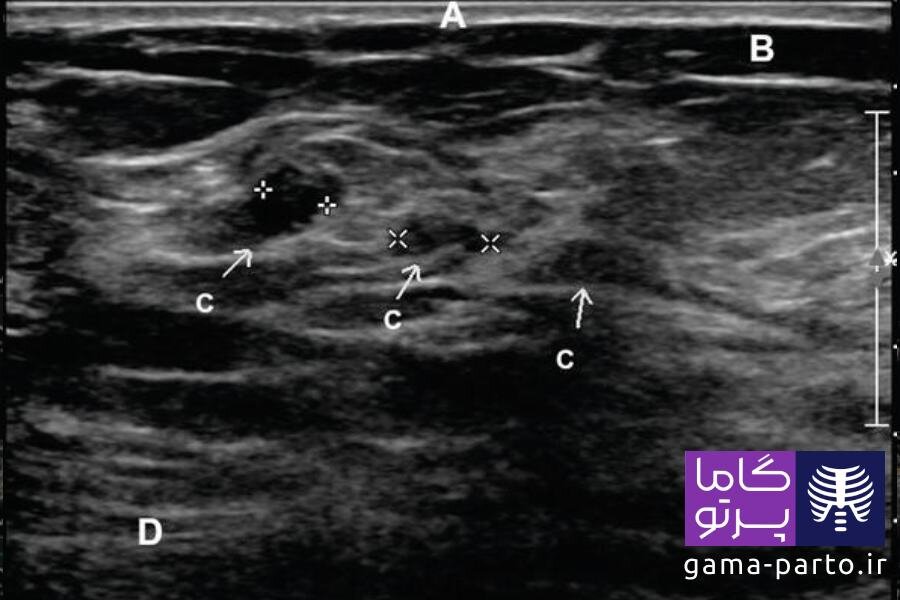

سرطان پستان در سونوگرافی چگونه است؟

در تصاویر سونوگرافی سرطان سینه، کیستهای پر از مایع معمولا به شکل دایرهها یا بیضیهای کاملا سیاه دیده میشوند. این در حالی است که تودههای سرطانی در مقایسه با کیستها معمولا کمی روشنتر و با لبههای نامنظم دیده میشوند.

تودههای مشکوک ممکن است دارای شکل نامنظم، حاشیههای نامشخص یا رشد در جهات مختلف باشند. با این حال، تشخیص سرطان پستان تنها بر اساس سونوگرافی سینه ممکن نیست.

بسیاری از تودههای غیرطبیعی ممکن است خوشخیم باشند. پزشک متخصص بر اساس شکل، تراکم و سایر ویژگیهای تصویری تودهها تصمیم میگیرد که آیا به آزمایشهای تکمیلی مانند بیوپسی یا ماموگرافی نیاز است یا خیر.